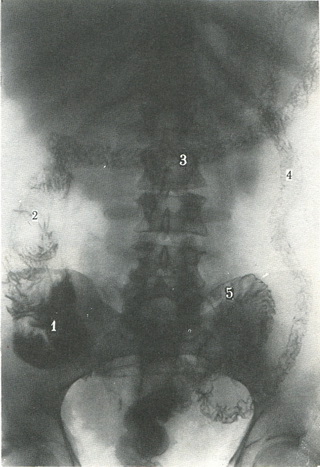

259. Оглядова рентгенограма рельєфу внутрішньої поверхні товстої кишки. 1 - сліпа кишка; 2 - висхідна кишка; 3 - поперечна ободова кишка; 4 - низхідна кишка; 5 - сигмовидна кишка; 6 - пряма кишка. |